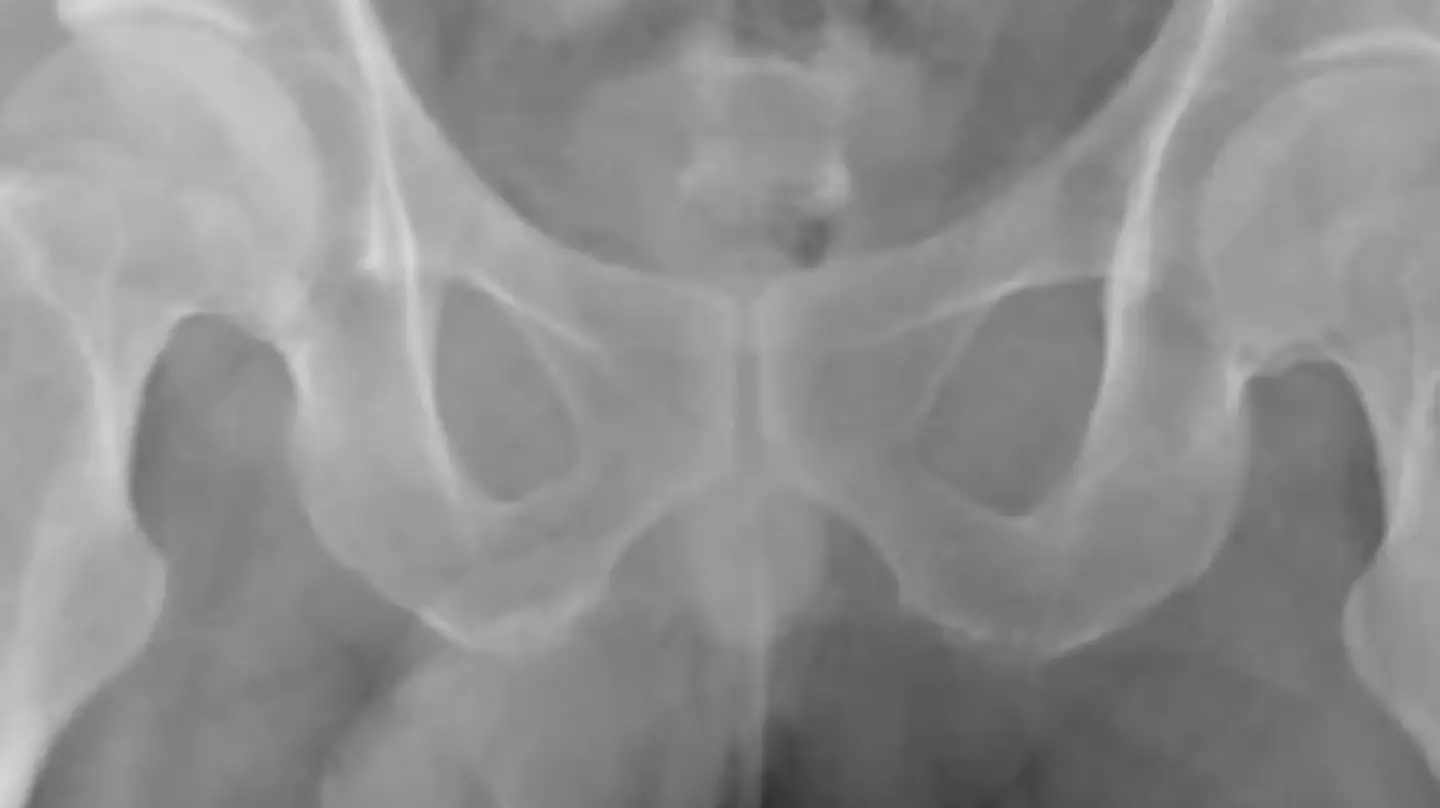

After experiencing problems urinating and severe abdominal pain which lasted for two hours, the man went to a hospital in Surabaya, Indonesia.

After an unsuccessful first attempt to remove the string, doctors decided to insert a camera into the man's bladder. This showed a 'black bundle of string' which meant that medics were able to use forceps after giving him local anaesthetic.